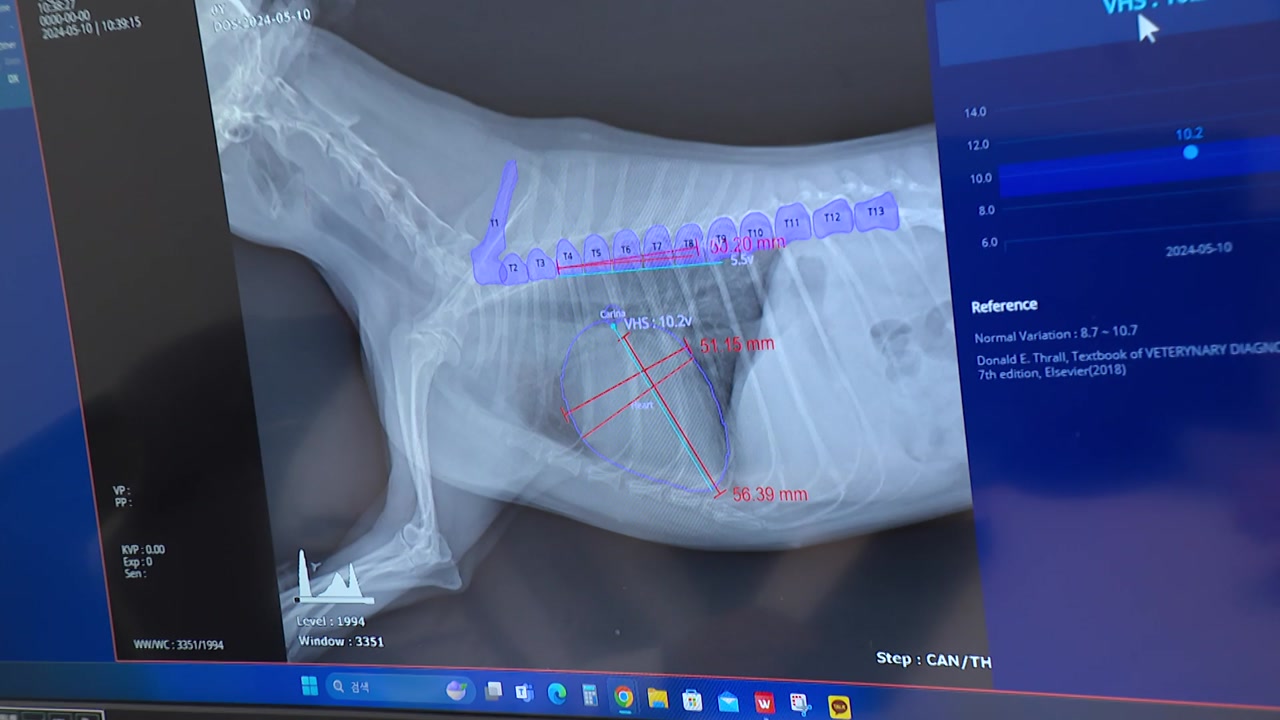

건강 문제로 동물병원을 찾은 7살 소형견.

엑스레이로 질병을 찾고 있습니다.

수의사가 화면의 버튼을 누르자 심장 크기 등 주의할 부분이 상세히 체크됩니다.

반려견의 엑스레이를 판독한 건 다름 아닌 인공지능, AI입니다.

[오이세 / 수의사 : 예전에는 수의사가 일일이 그걸 손으로 수치를 측정을 해서 그 심장의 크기를 평가했다면 지금은 이 인공지능을 통해서 15초 만에 결괏값을 확인할 수가 있기 때문에, 예전의 방사선 사진은 주관식 문제였다면 AI가 도입되면서 객관식 문제로 바뀌었다….]

영상 진단 보조 AI는 심장 질병 외에도 슬개골 탈구 등 47종의 질병을 확인할 수 있습니다.

영상 판독 전문 수의사와 진단과 비교했을 때 높은 일치율도 보였습니다.